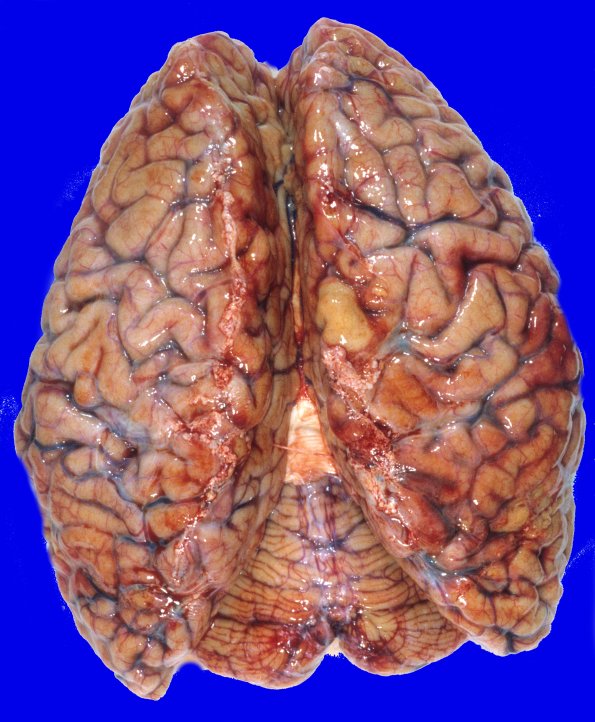

5A1,2 At autopsy the weight of the unfixed brain is 1010g. The dorsal and ventral view of her brain show cerebral and cerebellar atrophy.